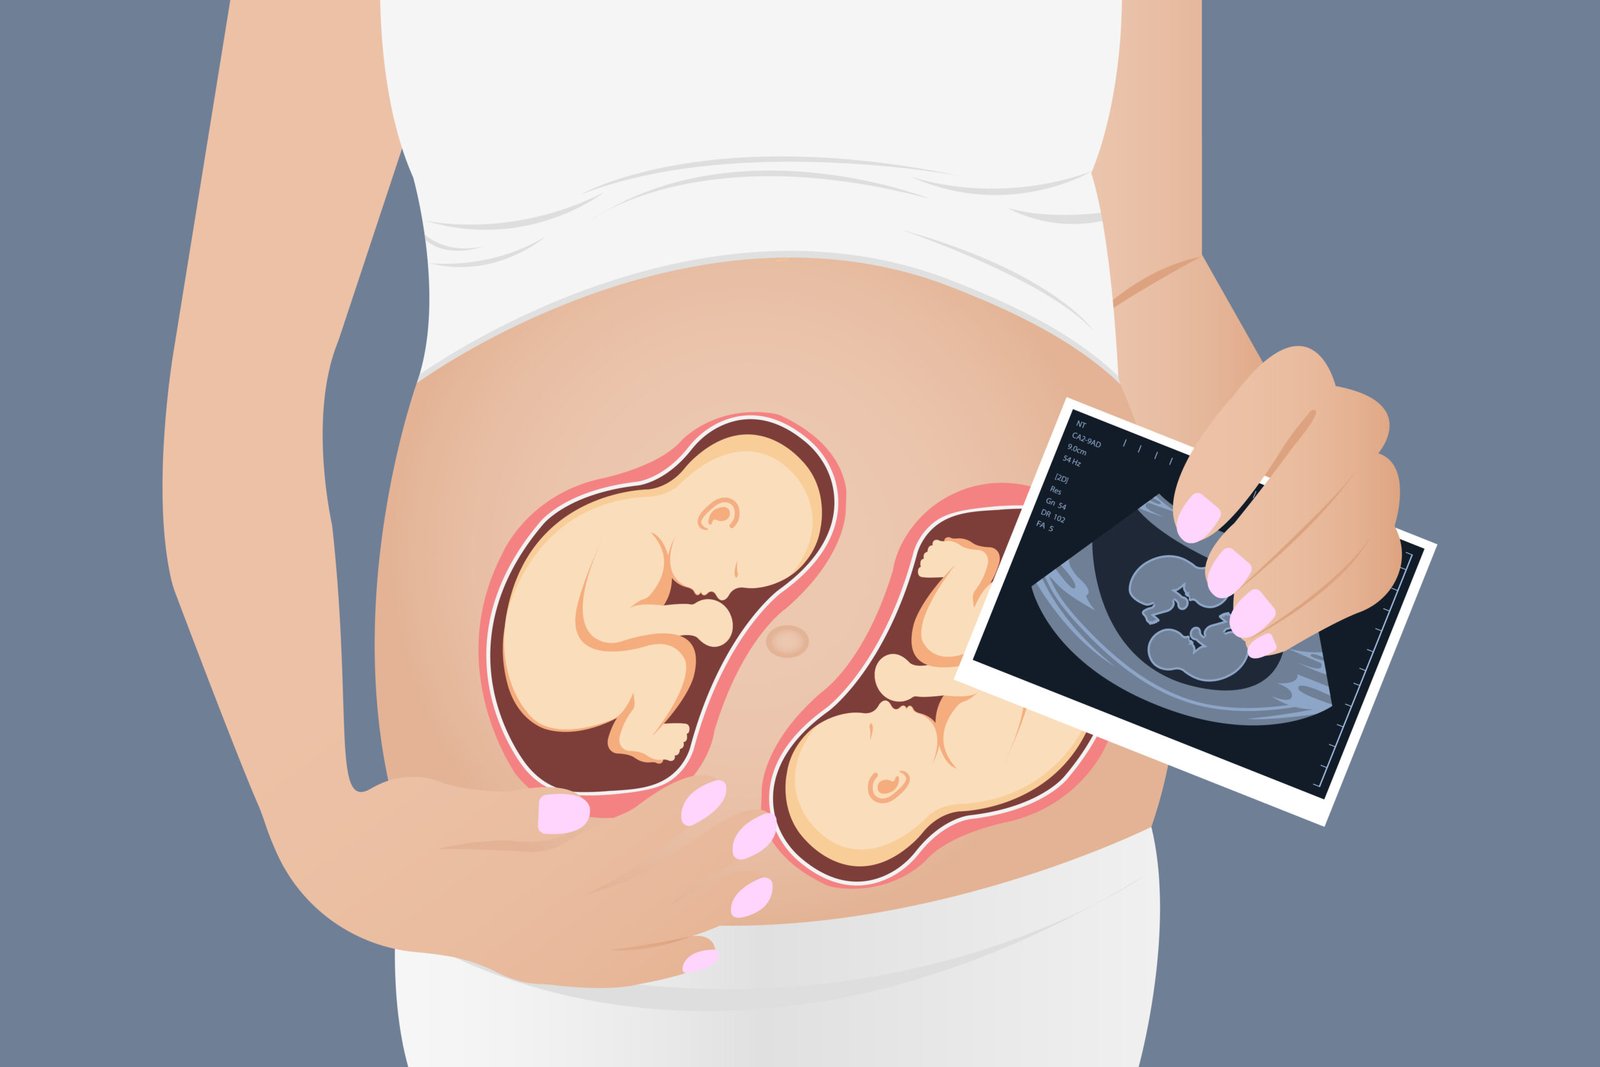

Twin Pregnancy

Expecting twins is a unique and exciting journey that requires specialized care to ensure the health and well-being of both the mother and the babies. Dr. Swathi Women’s Clinic is committed to providing comprehensive care for mothers of multiples, addressing the specific challenges associated with twin pregnancies. T